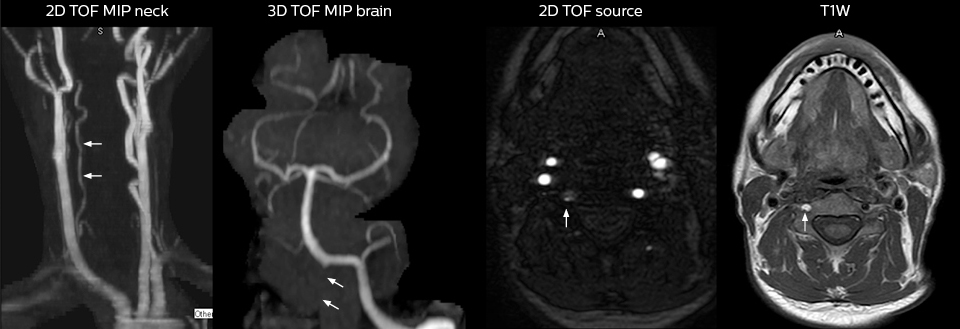

This patient presented with headache that was worse with neck flexion and we see a Chiari 1 malformation with low-lying cerebellar tonsils as well as some degenerative cervical thrombolytic change.